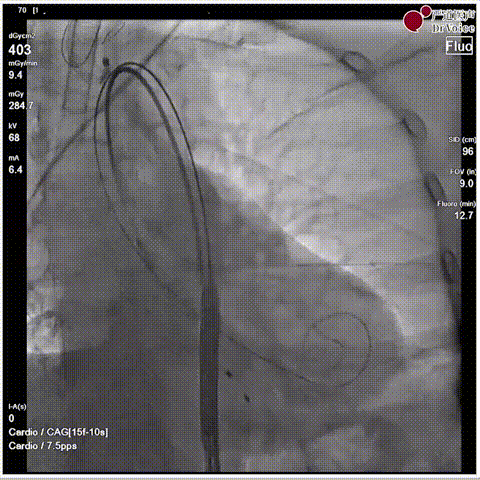

手术瓣膜释放后造影(4例)

病例一

病例二

病例三

病例四

快速过弓跨瓣(4例)